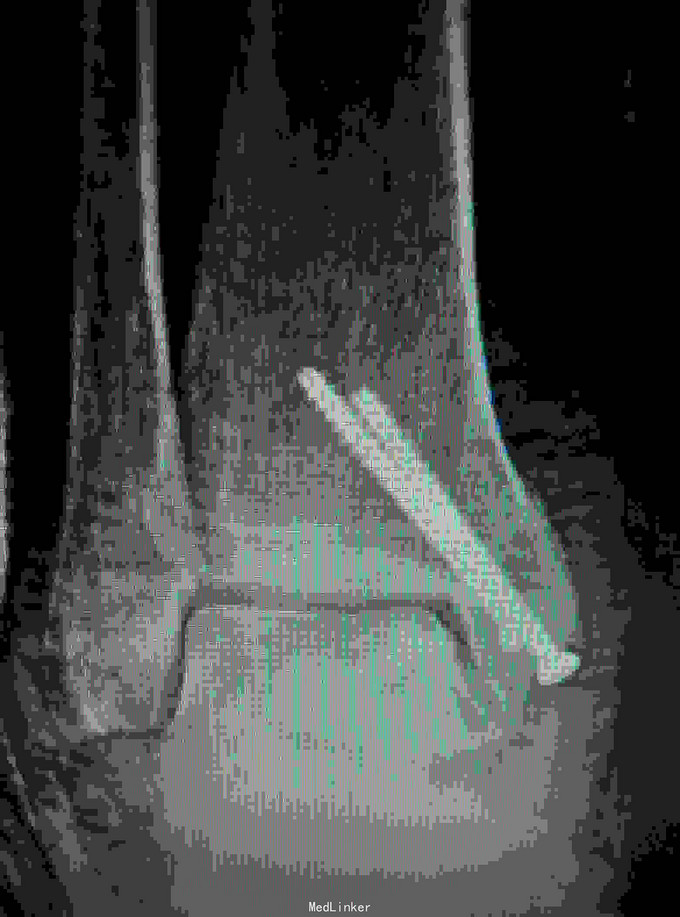

诊断是右距骨粉碎性骨折。给予行内踝截骨显露骨折端进行复位,采用Herbert钉进行固定。

术后复查X线片提示骨折端完全复位,内固定固定在位良好。 讨论:距骨骨折的主要并发症是坏死,骨不愈合等,但近年来随着对其认识的不断明确,治疗比较规范,积极的进行切开复位,并行坚强固定,近年的研究报告提示距骨的坏死率是不断在下降的,当然前提是进行有效复位并坚强固定。